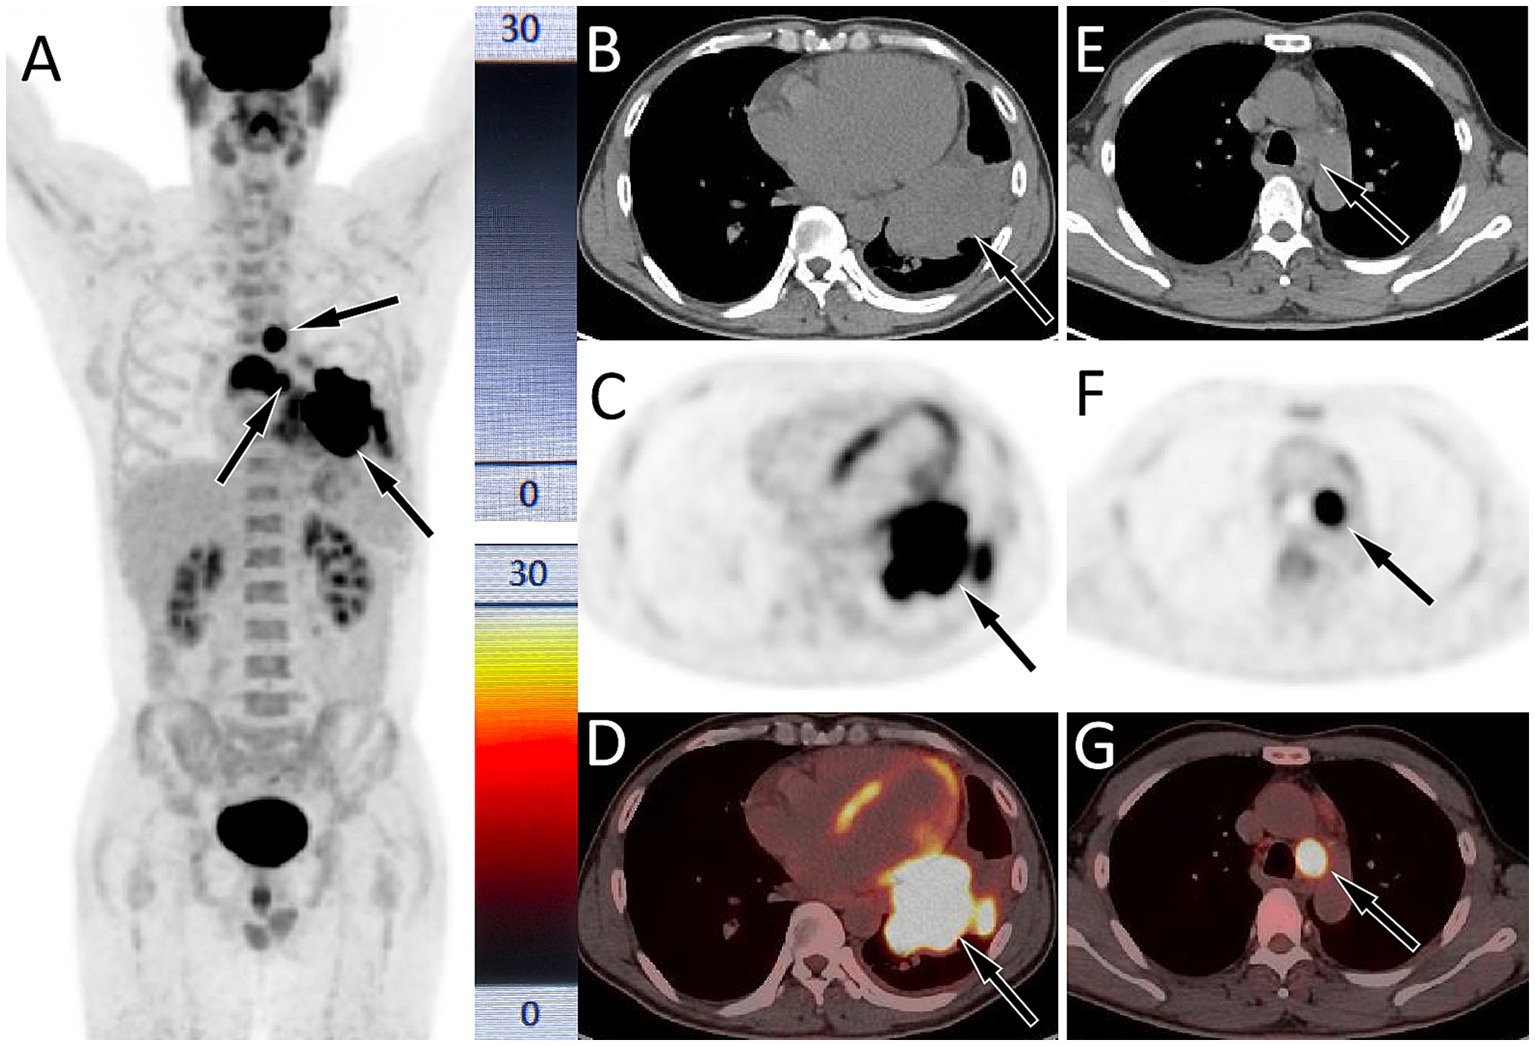

A 47-year-old male patient presented to our respiratory clinic on August 14, 2020, with complaints of chest pain for 1 month, cough, and shortness of breath for 5 days. The patient had a significant smoking history of 20–40 cigarettes per day. Both the patient and his family denied any personal or familial history of cancer. Physical examination revealed percussion tenderness over the left side of his chest, with no other positive signs. Lung tumor markers showed elevated levels of neuronal enolase (39.4 ng/mL; normal reference value less than 16.3 ng/mL) and squamous cell carcinoma antigen (4.6 ng/mL; normal value less than 1.5 ng/mL). A chest CT scan demonstrated a mass in the left hilar region of the lung with associated left-sided obstructive pneumonia. PET/CT imaging (as shown in Figure 1) revealed significantly increased 18F-FDG uptake in the left lung mass, accompanied by multiple foci of elevated glucose metabolism in the mediastinal and left hilar lymph nodes. Additionally, thickening of the left pleura with increased glucose metabolism was observed, suggesting the possibility of lung cancer with left pleural metastasis, mediastinal lymph node metastasis, and left hilar lymph node involvement.

Figure 1. Fluorine-18 fluorodeoxyglucose (18F-FDG, with 314.5 MBq of injected activity) positron emission tomography (PET)/CT imaging of the patient on August 24, 2020; The maximum intensity projection (MIP, A) showed multiple significantly increased 18F-FDG uptake in the chest (arrows). Axial CT (B) showed a soft tissue density mass in the left portal area of the lung (arrow). The corresponding lesion had significantly increased 18F-FDG uptake on axial PET (C, arrow) and PET/CT fusion (D, arrow), with a maximum standardized uptake value (SUVmax) of 29.5. (E) Axial CT also showed an enlarged lymph node in the mediastinum, with a short-axis of about 2.0 cm; which was significantly increased 18FDG uptake on PET (F) and PET/CT (G), with a SUVmax of 25.3.